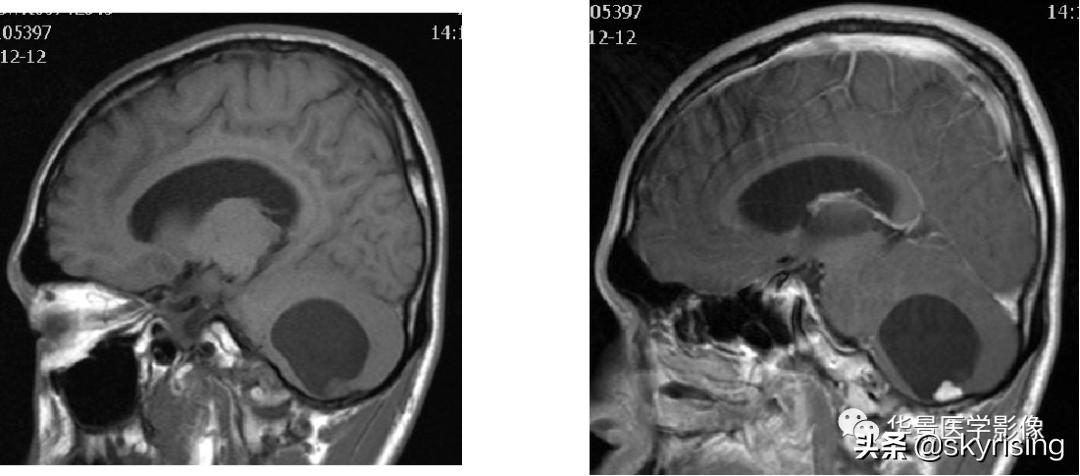

上图白色箭头:小脑延髓池内延髓背侧不规则形团块影,小脑半球、延髓、第四脑室受压变形,所见诸脑室未见增宽。

蓝色箭头:延髓受压前后径变窄,T1信号减低,考虑合并水肿。

黄色箭头:病灶边缘见流空信号血管影。